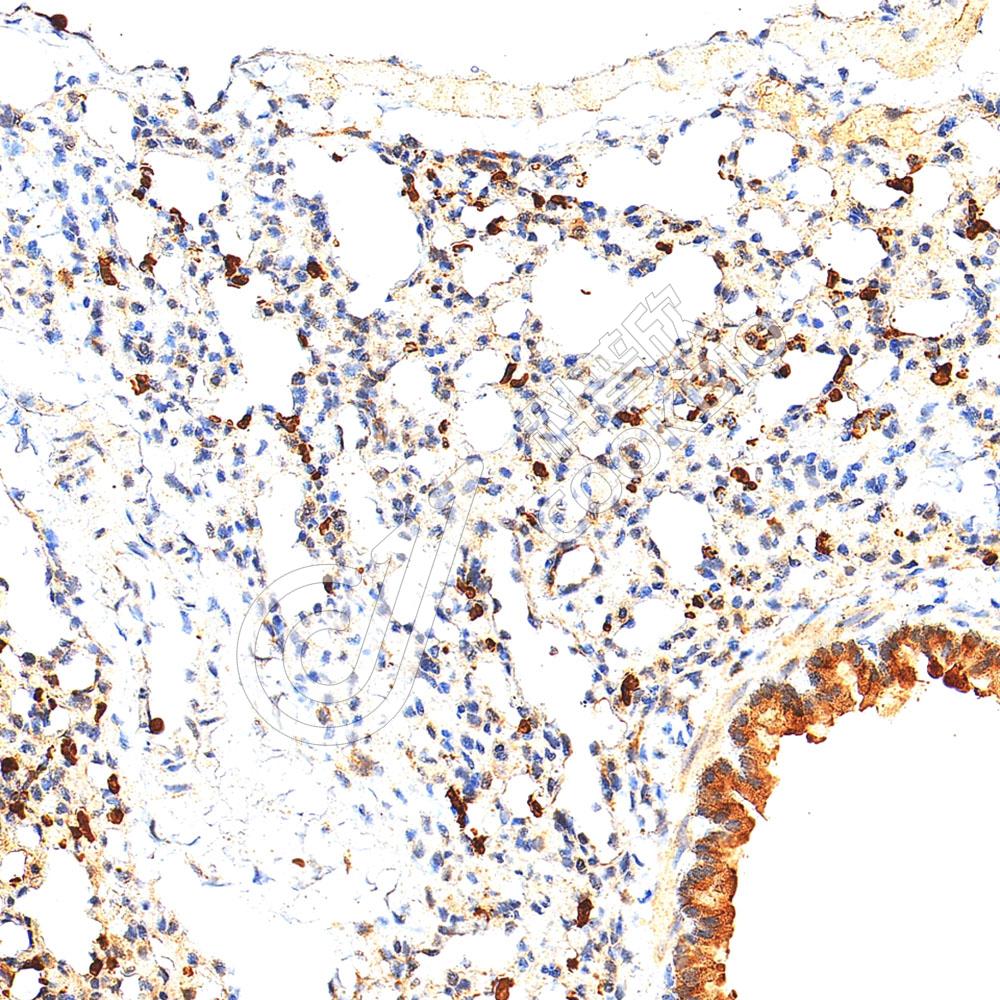

IHC检测TMEM147蛋白(货号 K1345918).

样品: 大鼠肺, 4%多聚甲醛 (货号KSG1101) 固定12-24小时.

抗原修复: Tris-EDTA抗原修复液(pH 9.0) (KSG1203), 98℃, 20分钟.

—抗: 1: 1600稀释, 4℃ 孵育过夜.

二抗: S-vision免疫组化多聚二抗(山羊抗兔),即用型 (货号KB3906), 室温孵育20分钟.